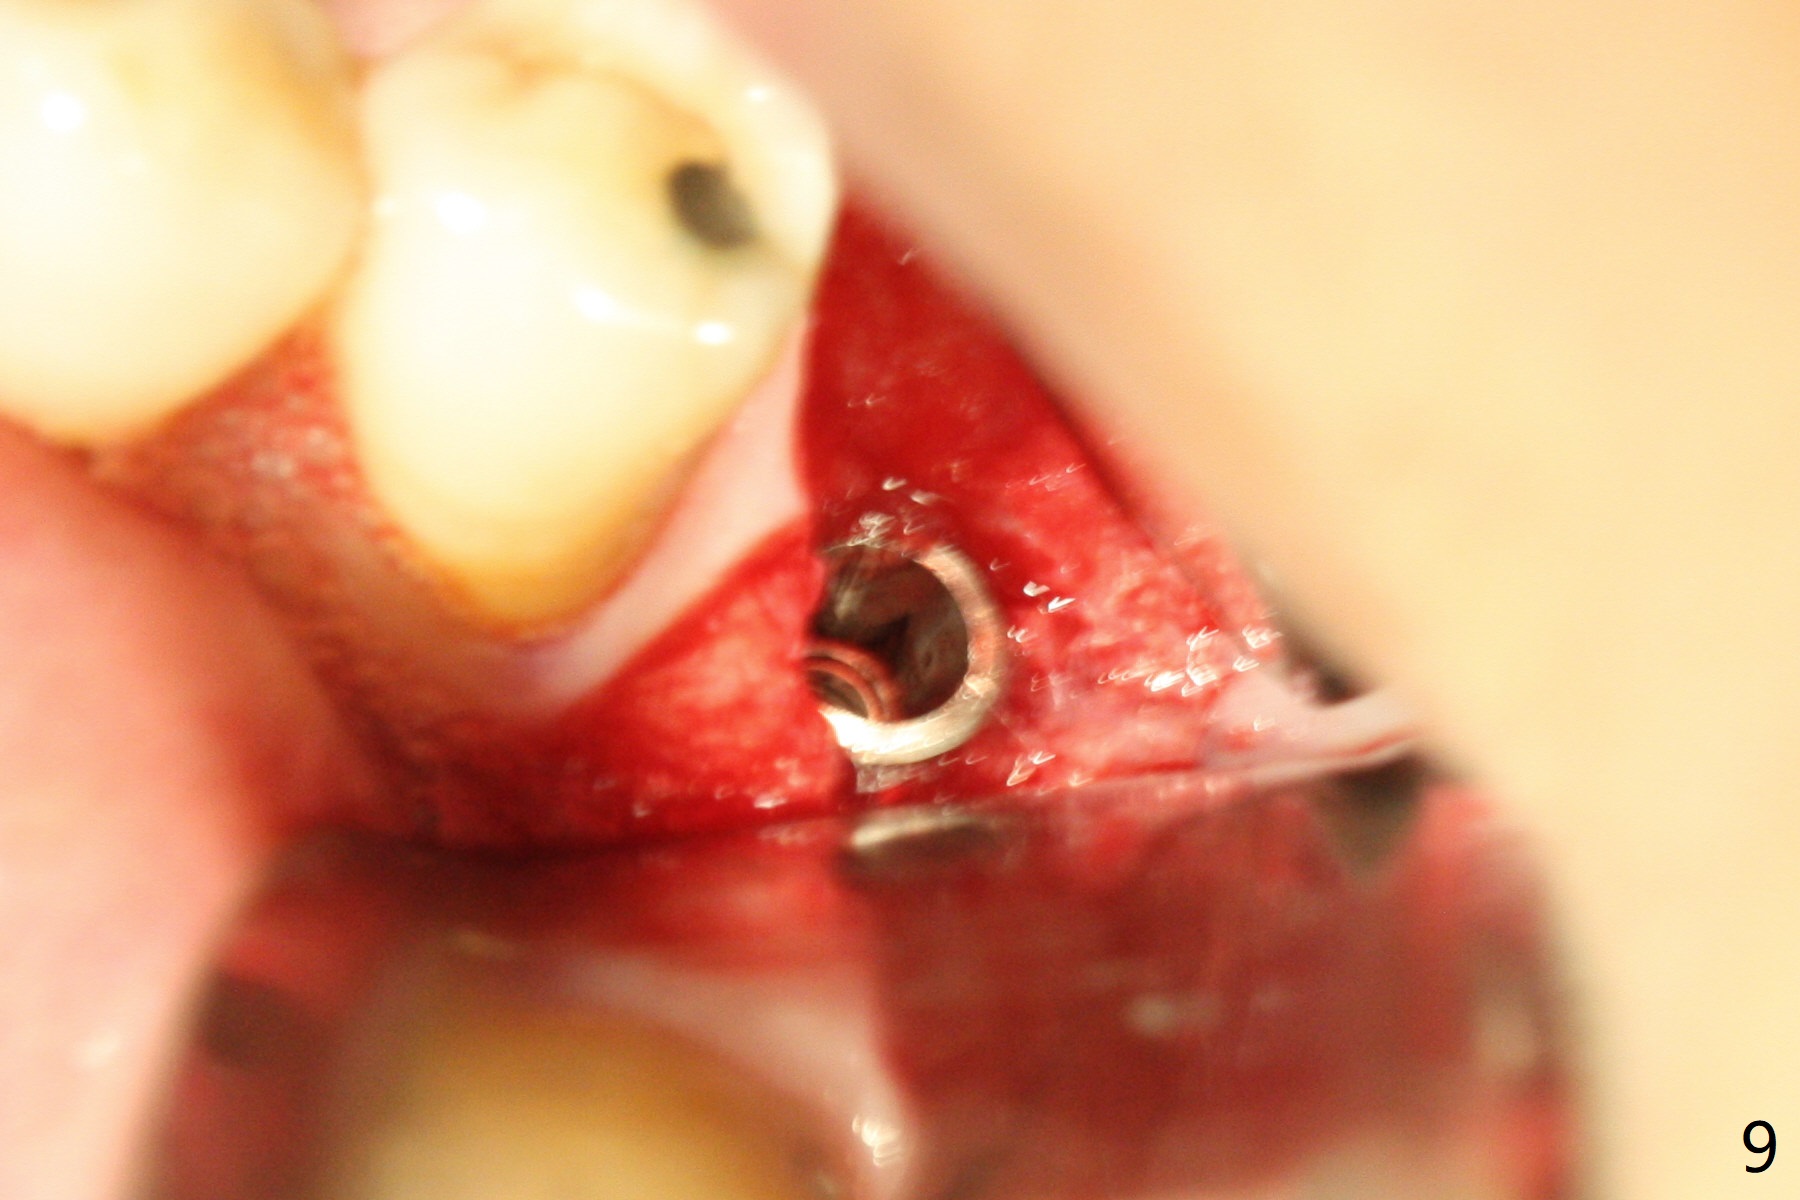

When the patient returns for treatment, the implant at #19 is mobile with tenderness (without purulence, Fig.1). She finally agrees to have CT taken (Fig.2,3 (coronal section (L: lingual))). The implant is removed after several carpules of cocktail anesthetics for infiltration and one carpule for block. Osteotomy is initiated in the mesial slope of the defect (Fig.2,4). The advantage of immediate implant re-placement is wide bone at the intended area (Fig.3). After change in trajectory (compare Fig.4 (4x11 mm dummy implant) and Fig.5), a 4.5x9 mm IBS implant is placed with insertion torque of 50 Ncm (Fig.5); with Osteogen plug placed in the distal defect, allograft (*) is placed immediately distal to the implant. With the longest cuff available (4 mm), the margin of the abutment (4.5x4(4) mm) is equi-crestal (>). When the 9 mm long implant is placed deep, the coronal threads of the implant are distally exposed (Fig.6 between arrowheads) less than those of the 11 mm one placed superficial (Fig.2). Intraoperative socket hemorrhage is controlled by packing gauze saturated with Epinephrine 1:50,000. The patient chooses not to take Medrol Dose Pack for postoperative edema. She removes periodontal dressing herself prematurely. The socket wound dehiscence is noted the first postop visit (7th day). Fig.7 is taken 9 days postop before re-suturing. The patient insists on removing the implant with dull pain. Three months 10 days postop, she returns with loss of the abutment and a fistula (Fig.8). In fact there is bone formation distal to the implant. Torque wrench has to used to remove the implant.